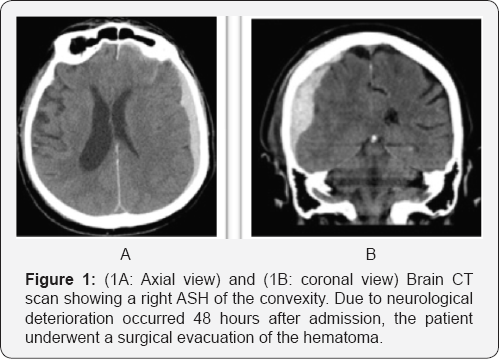

All 17 patients were initially treated conservatively. Three underwent an emergency craniotomy and evacuation of the ASH a few days after admission (range 24-56 hours), (Figure 1A & 1B) because of neurological deterioration and one patient died two days after admission for progressive increasing of the intracranial pressure. Among the rest of the patients treated medically (Figure 2) (13 patients) all out of two (11 patients) were transferred to a rehabilitation center or nursing home after a median of hospital staying of 23 days (range between 21 and 33 days). The other two were operated on for a chronic subdural hematoma (CSH) and a week postoperatively they were transferred back to the referring hospital. Also the three patients operated on for the ASH were transferred to a rehabilitation unit, just after a week from surgery. Among the 11 patients treated conservatively (Figure 2) and discharged from the neurosurgical ward, five (45%) were readmitted for the treatment of a developed CSH. All patients received IV steroids for a mean of 4 days (range 3-7) at the admission. In order to prevent thromboembolic events due to poor mobilization, we choose to start low molecular weight heparin (LMWH) 2 days after admission, but only in case the CT images were stable. All patients underwent a 12 hours post admission follow up CT scan or earlier in case of deterioration. A second scan was performed after 48-72 hours and then after a week and before the discharge as well as after 2, 4 and 6 weeks in order to detect the transformation from acute to CSH and any evidence of mass effect.

Among the 17 patients we tried to treat conservatively 1 died, 3 underwent an emergency craniotomy and evacuation of ASH. Thirteen were continuously treated conservatively. Among these, two patients were operated on for a CSH during the same in-hospital staying. One after 28 days and the other after 33 days from the trauma. Among the 11 patients discharged from the neurosurgical care, 5 were operated on for a CSH during a second admission and discharged back after a median time of 5 days; the remained 6 cases out of 17 (35,2%) were treated conservatively and at a median follow up of 11 months (range 8-14 months) they have a GOS between 2 and 5 (mean 3). At the same follow up the mean GOS for surgically treated patients was 2,9 (range 2-4).